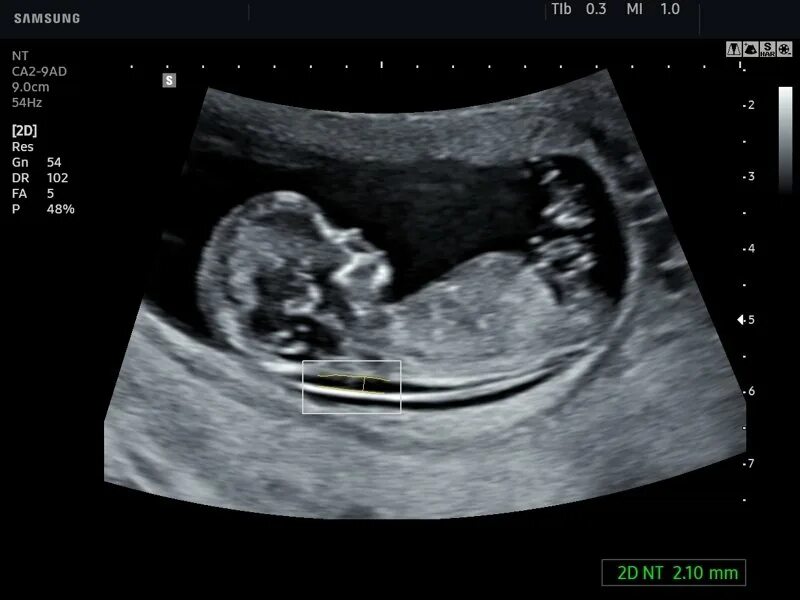

Воротниковое пространство 5